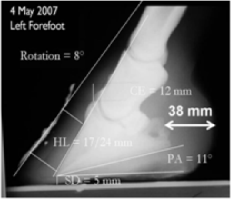

[Fig 1- 4 pictures below] Before taking radiographs, the investigators used the CS measurements to predict 3 degree palmar angle and a 16mm sole depth

The radiograph below verified that the predictions were reasonably accurate. The accuracy of these predictions is made possible by the consistency of the externally visible collateral sulci to the third phalanx [red arrow below]